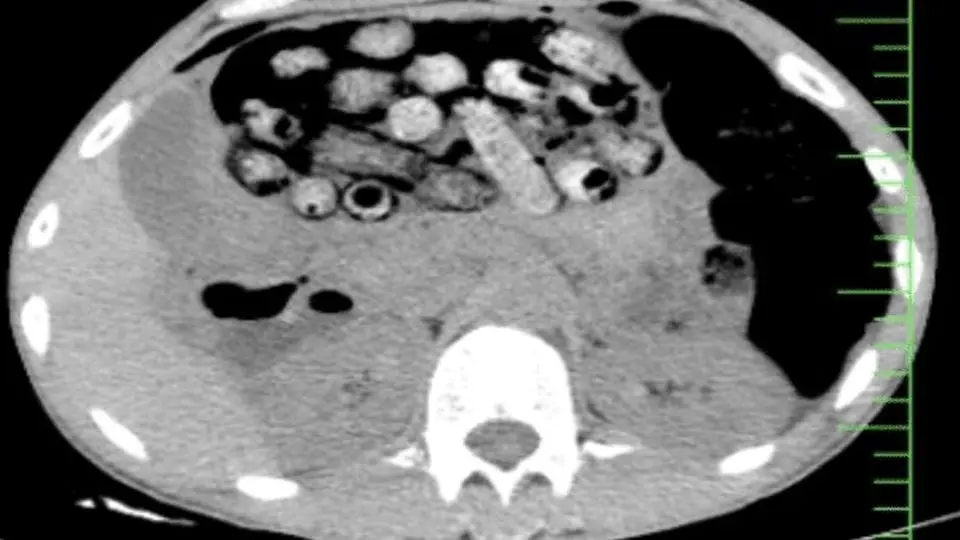

بر اساس اظهارات مأمور همراه، این فرد پیش از مراجعه اقدام به بلع تعدادی بسته محتوی مواد مخدر کرده بود که در پی انجام تصویربرداری، تعداد زیادی بسته مشکوک در معده و روده کوچک و بزرگ وی مشاهده شد.

با توجه به خطر پارگی احتمالی بسته‌ها و احتمال بروز عوارض تهدیدکننده حیات، بیمار بلافاصله به اتاق عمل منتقل شد و جراحی سنگینی از ساعت ۳ بامداد آغاز گردید.

این عمل جراحی به سرپرستی عضو هیأت علمی گروه جراحی عمومی دانشگاه علوم پزشکی البرز و با همکاری گروه‌های اورژانس، تصویربرداری، بیهوشی و جراحی انجام شد که درنهایت بیش از ۹۰ بسته مواد مخدر از معده و روده بیمار خارج شد.